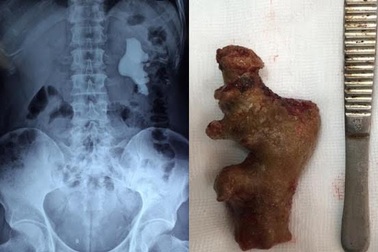

Uống thuốc nam 10 năm, sỏi "đúc khuôn" trong thậnCách đây 10 năm, bệnh nhân được phát hiện sỏi thận nhưng không can thiệp, tự mua thuốc nam để uống tại nhà. Đến khi xuất hiện đau tăng dần, đến lúc đau dữ dội không chịu nổi, bệnh nhân đến viện được bác sĩ phẫu thuật lấy da viên sỏi dài đến 11cm.